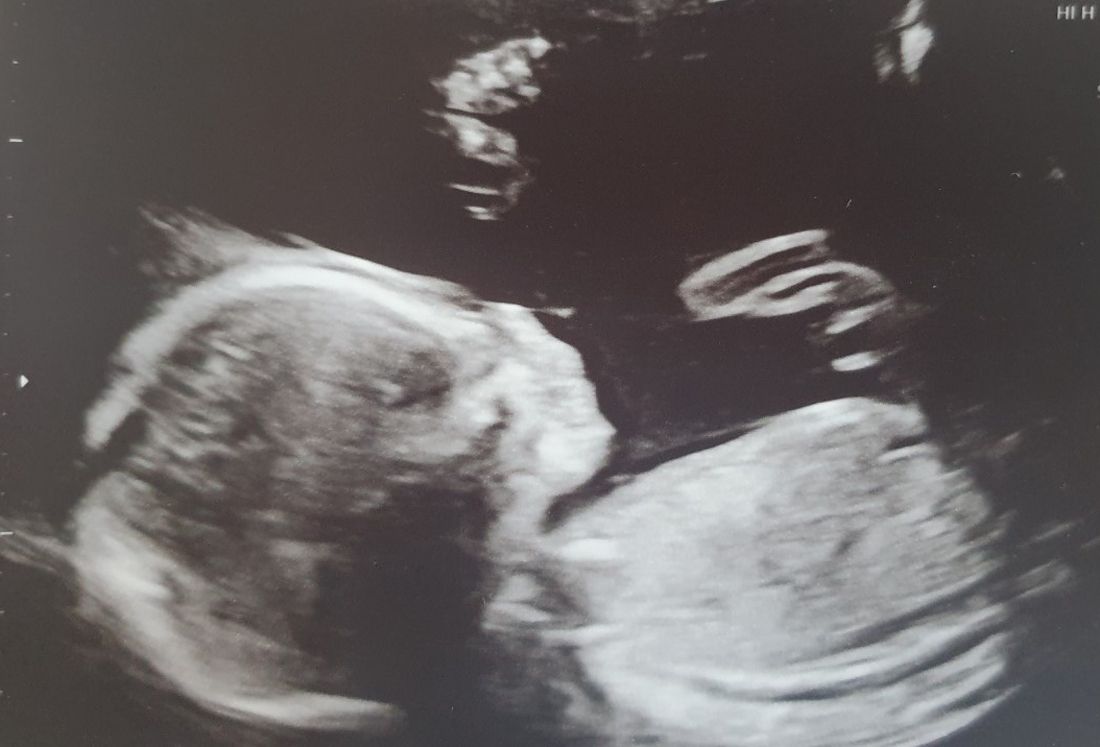

Thankfully, nothing went wrong, and Danielle is now 24 weeks pregnant with a baby girl.

“For the first few weeks I was so nervous, but now I'm excited," she said.

She added: “It felt amazing to see her heart beat for the first time and my little girl is giving me a hard time with all the kicking. She's always booting me – but I wouldn't have it any other way."